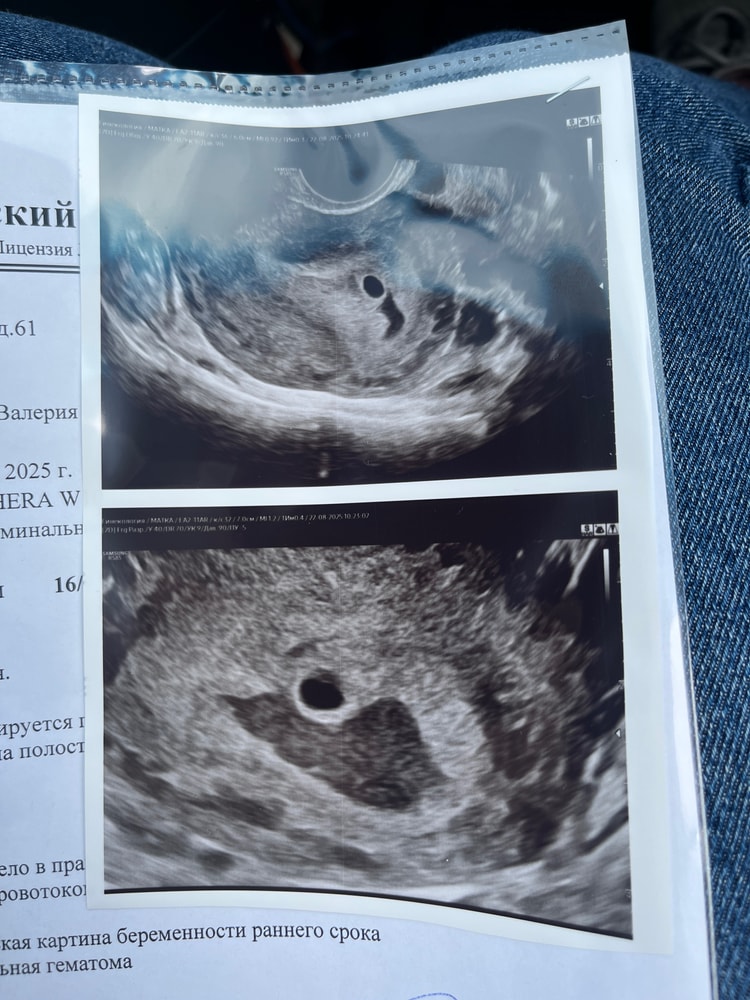

Хорошо что записать на узи, нашли большую гематому, плодное яйцо 6мм, ЖМ нет, повтор узи в жк 29 числа, а платно 5 сентября, у кого-нибудь были большие гематомы, долго рассасывалось?

Черный участок под плодным яйцом это гематома

Мария sanare, по узи 5н 3д, а по календарю 5н 2д

У вас гематома действительно большая.